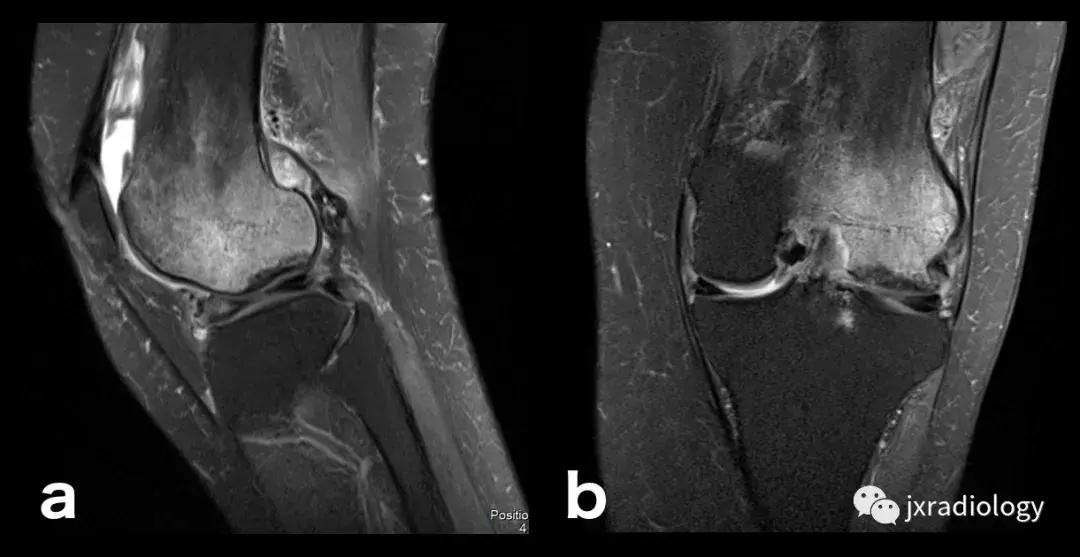

图26:局限性游走性骨质疏松症(具有位置变化的短暂性骨髓水肿综合征)(连续冠状PD-FS-WI):在一些情况下,在连续MRI上看到骨髓水肿的位置变化,这被称为局限性游走性骨质疏松症(RMO);尽管可以自愈的短暂性骨髓水肿综合征的情况更为常见,但可以在一小部分病例中转移到不同的关节,或者(甚至更罕见)转移到同一关节内的不同部位(关节内转移) ,如关于该患者所见。在这个关节内RMO病例中,没有创伤史,水肿始于股骨内侧髁,3个月后发现转移到外侧髁。